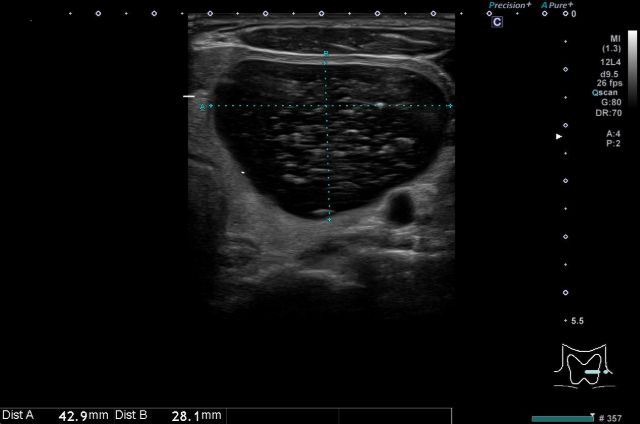

エコー所見では、濾胞性腫瘍は単発性で、被膜がはっきりしていること、腫瘍内部は均一なことが多いとされています。濾胞がんでは濾胞腺腫と比べると、被膜が不整であったり、腫瘍の辺縁が硬いことが多いとされています。

③濾胞(ろほう)性腫瘍(濾胞腺腫、濾胞がん)

濾胞性腫瘍は、良性の濾胞腺腫と悪性の濾胞がんに分類されますが、甲状腺針細胞診で両者の鑑別は基本的にはできないため、針細胞診で濾胞性腫瘍と判断された場合で、4cm未満で転移がない場合はサイズフォローをし、4cmを超えた場合は濾胞がんの可能性が高くなるため診断的治療目的で手術が検討されます(外科的切除後、腫瘍細胞が被膜を超えている場合や血管内浸潤している場合に、濾胞がんと診断されます)。